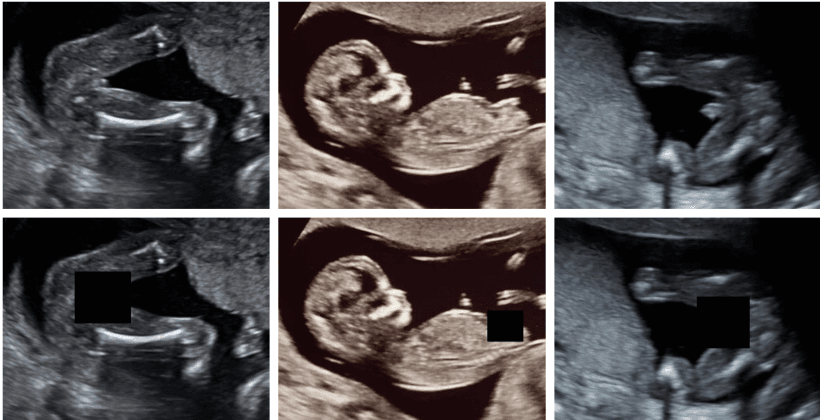

Fetal Gender Masking

Deep learning approach for automatically masking fetal gender indicators in ultrasound imagery to support blind studies. Uses segmentation networks trained on medical imaging data to ensure privacy compliance in prenatal research.